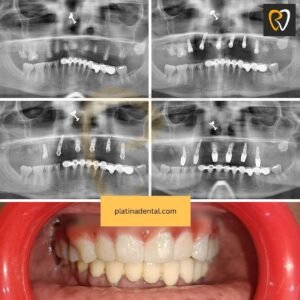

3️⃣ Full Mouth Dental Implants

For patients missing most or all teeth, full mouth implant solutions restore complete function and aesthetics. This is a stable alternative to removable dentures.

With regular monthly checkups we ensure that our high implant success rate is maintained